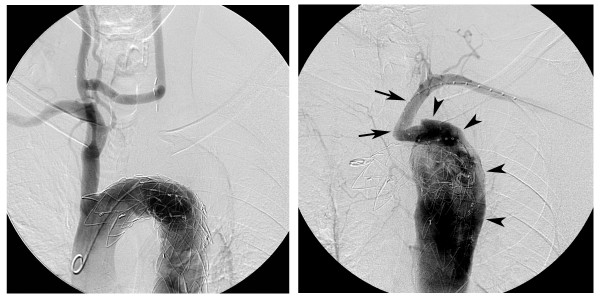

3 - دست های همیشه سرد به دلیل بیماری برگر یا ترومبوآنژئیت انسدادی

ترومبوآنژئیت انسدادی ( بورگر / برگر ) [1] نادر است که معمولا به دلیل مصرف سیگار و تنباکو ایجاد می شود . در این بیماری شریان ها و رگ های دست ها و پاها ملتهب یا متورم شده و گاهی لخته های خونی در رگ ها ایجاد می شود . علائمی مانند درد و حساسیت در دست ها و پاها و همچنین سرد بودن دست ها و پاها میتواند به دلیل بیماری ترومبوآنژئیت انسدادی باشد .